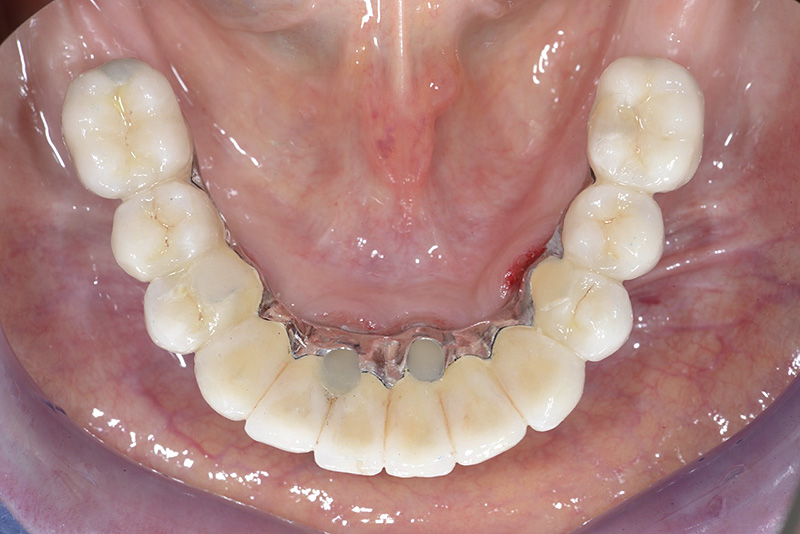

Vengono utilizzati 2 tipi di provvisori: il primo, cementato ai denti vicini, viene utilizzato dal momento dell’estrazione del dente fino ad impianto osteointegrato (circa 6 mesi); il secondo, avvitato direttamente all’impianto, ha una funzione di prova estetica ma soprattutto di guida per la maturazione dei tessuti gengivali peri-implantari portandoli verso la maturazione completa prima di posizionare la corona finale in disilicato di litio.